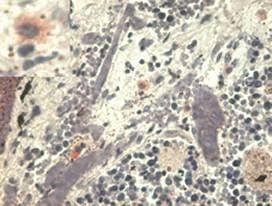

Mouse Monoclonal HLAG antibody. Suitable for WB, IHC-P and reacts with Human samples. Cited in 25 publications. Immunogen corresponding to Recombinant Full Length Protein corresponding to Human HLA-G.

Applications IHC-P, WB